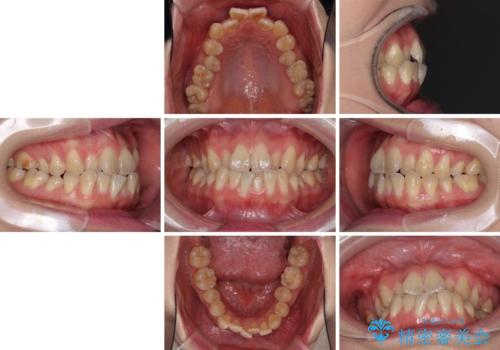

ハーフリンガル 反対咬合の改善

- 20代女性

- ハーフリンガル

- 1年9ヶ月

- 前歯の反対咬合を気にして来院された患者様です。

目立ちにくい装置での治療をご希望とのことで、上顎が裏側装置、下顎が表側装置のハーフリンガルにより矯正治療を行うこととしました。

下顎の歯列全体を後方に動かす場合、さまざまリスクを伴うため慎重に行う必要があり、さらには移動量に限界があるため、治療計画は無理のないものとしなければなりません。

下顎左右の奥にアンカーボルトを使用して、無理のない範囲で後方に移動させ、きれいに仕上げることができました。